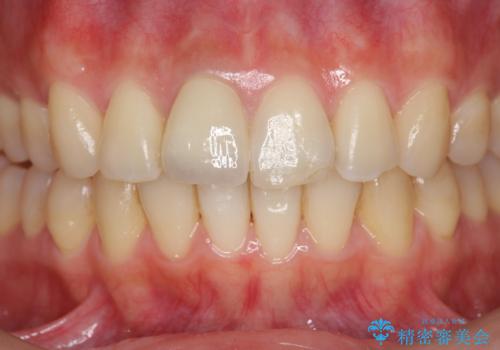

前歯の変色 打撲により失活した前歯の根管・セラミック治療

- 変色してきた前歯の形態回復、色調の改善を求めて来院されました。

X線検査、歯髄(歯の神経)の検査を行ったところ、失活(歯の神経の死んだ状態)であると診断されました。

放置すると変色が進行するだけでなく、根尖病変も形成される恐れが強いことから、根管治療を行ったのちセラミッククラウンによる審美性の改善を計画します。

自然な色調をセラミッククラウンで再現することができ、審美性の改善に大変喜んでいただくことができました。